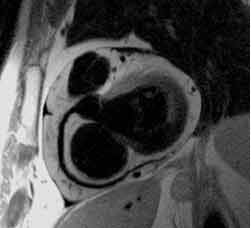

MRT des Herzens

Die MRT des Herzens (Cardio-MRT) erlaubt ohne Strahlenbelastung und ohne Katheter hervorragende Aussagen über

• Funktion der rechten und linken Herzkammer und des Herzmuskels

• Herzfehler

• Tumore des Herzens

• Durchblutung des Herzmuskels

• Abgrenzung von Infarktnaben des Herzmuskels gegen lebendes Muskelgewebe

• Herzklappenfehler

Die MRT des Herzens benötigt einen besonders schnellen Scanner, der trotz komplizierter Herzbewegungen ultraschnelle Aufnahmen anfertigen kann.